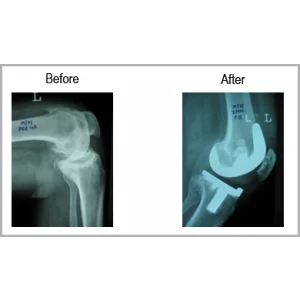

A male aged 65 years primarily treated in Kenya for fracture of tibia right, also had osteoarthritis of both knee. He was not able to put any weight over right leg.

His fracture and arthritis were treated with knee replacement with fracture fixation in a single surgery. Today his legs are normal and he can swim, walk and perform all his activities without any assistance.